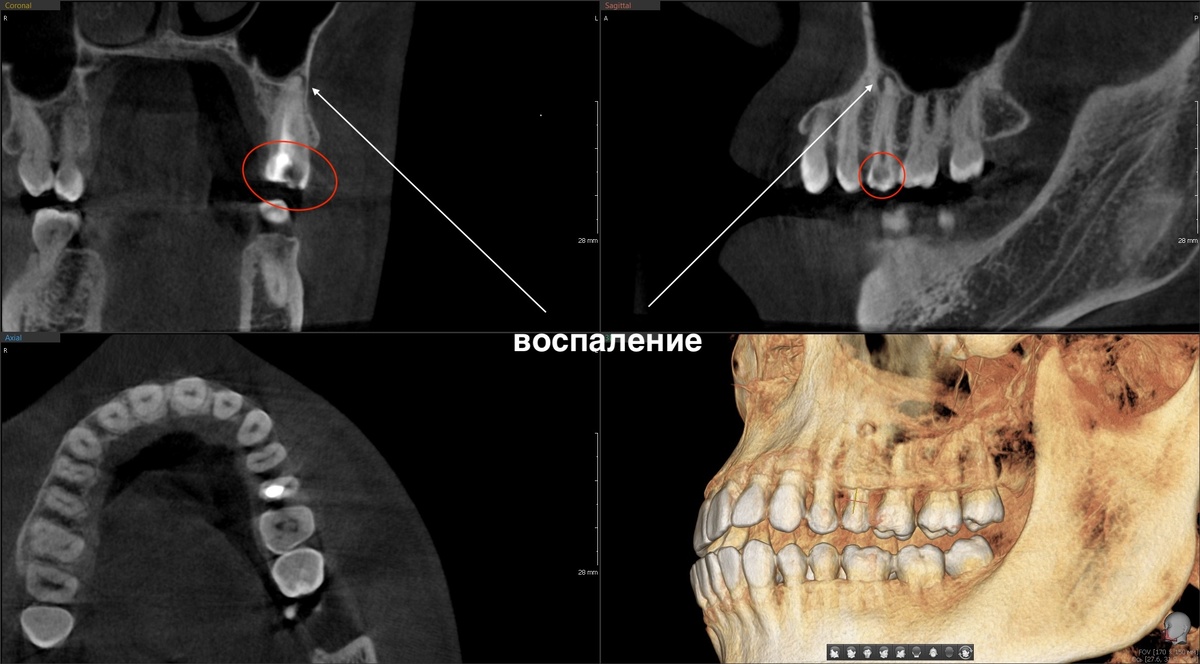

Оцениваем КТ, периодонтит 2.5 зуба зажил:

За это время зуб жил, служил, не беспокоил. Кость восстанавливалась - именно так и должно работать качественное эндодонтическое лечение. Нужно создать условия для того, чтобы организм сам себя починил - и он починит.